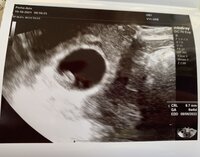

Vaikka ajatustasolla tilannetta ei pitäisi olla ja kaikki on huonosti, niin kyllä siellä syke oli ja vastasi arvioita. Laskettu aika tämän hetken tiedoilla meni päivän taaksepäin, eli 9.6.

Jee, mahtavaa! Onnea! Beating HeartNiin vaan näkyi hyvin vahva ja tasainen syke tänään ultrassa Beating Heart pituutta oli 10,6mm mikä vastasi viikkoja 7+1 eli juuri se mitä itsekkin kierron mukaan arvioin :)

Ihana uutinen! Beating HeartVaikka ajatustasolla tilannetta ei pitäisi olla ja kaikki on huonosti, niin kyllä siellä syke oli ja vastasi arvioita. Laskettu aika tämän hetken tiedoilla meni päivän taaksepäin, eli 9.6.